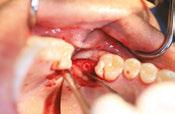

get connected. Intraoral scans are done again after the surgery (Figure 6), and pre- and post-surgery scans are overlapped to mill the PMMA teeth the day of the surgery. While I do own a 3D printer, I like milled PMMAs more since that provides more shade options with the lighter colors. I also find milled PMMAs are stronger than the printed PMMAs.

PMMA gets milled (Figure 7) and delivered the day of the surgery with a very passive fit (Figures 8 and 9).

I use this digital immediate-loading technique right after implant surgery for the temporary teeth to be fabricated on the same day of surgery. However, on some cases with the same technique, I can directly mill final teeth from zirconia right after the surgery as well. So, whether I place temporary or permanent teeth, the technique is the same. More often I fabricate temporary teeth because of the soft tissue changes following surgery during the healing time. I choose to delay the permanent teeth fabrication from zirconia the day of the surgery to give more time for soft tissue healing and settling. IP

Figure 7: Milled PMMA Figure 8: Inserted PMMA on the day of the surgery. Figure 9: Patient’s pre- and postoperative pictures Figure 10: Dr. Samantha Siranli (prosthodontist), Tony Yoo (CAD/CAM specialist), Shyun Oh (master ceramist)